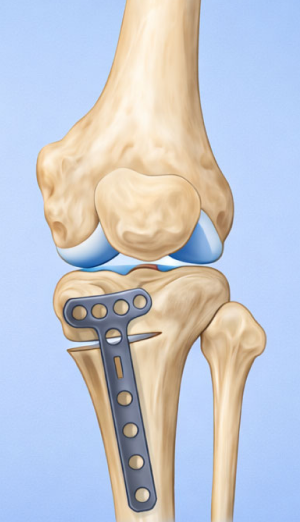

High Tibial Osteotomy (HTO)무릎 아래 뼈인 경골(정강이뼈)의 윗부분(근위부)을 절골하여 다리 정렬을 바로잡는 무릎 교정 수술입니다.

무릎 안쪽 관절이 닳아 O자 다리 형태로 휘어 통증이 생기는 경우, 다리의 축을 바로잡아 무릎 안쪽의 하중을 줄여주는 교정 수술입니다.

관절면과 평행하게 절골하여 각도를 교정

근위경골 절골술 교정 후

정강이 위쪽 뼈(경골 근위부)를 절골합니다.

약간 벌리거나 닫아서 다리축을 “일자에 가깝게” 교정해서 닳은 안쪽 무릎의 부담을 줄이고 통증 감소 및 기능 향상을 유도합니다.

절골한 부위는 금속판(plate)으로 고정합니다.

시간이 지나면 뼈가 붙습니다.